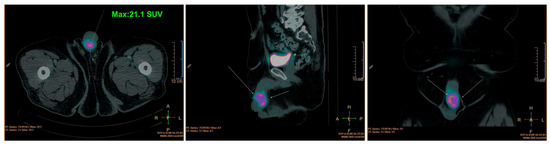

2. Case Presentation